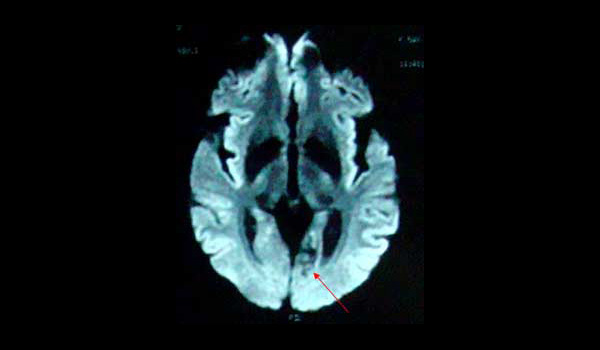

IRM difusión axial: malformación arteriovenosa en el giro fusiforme izquierdo.